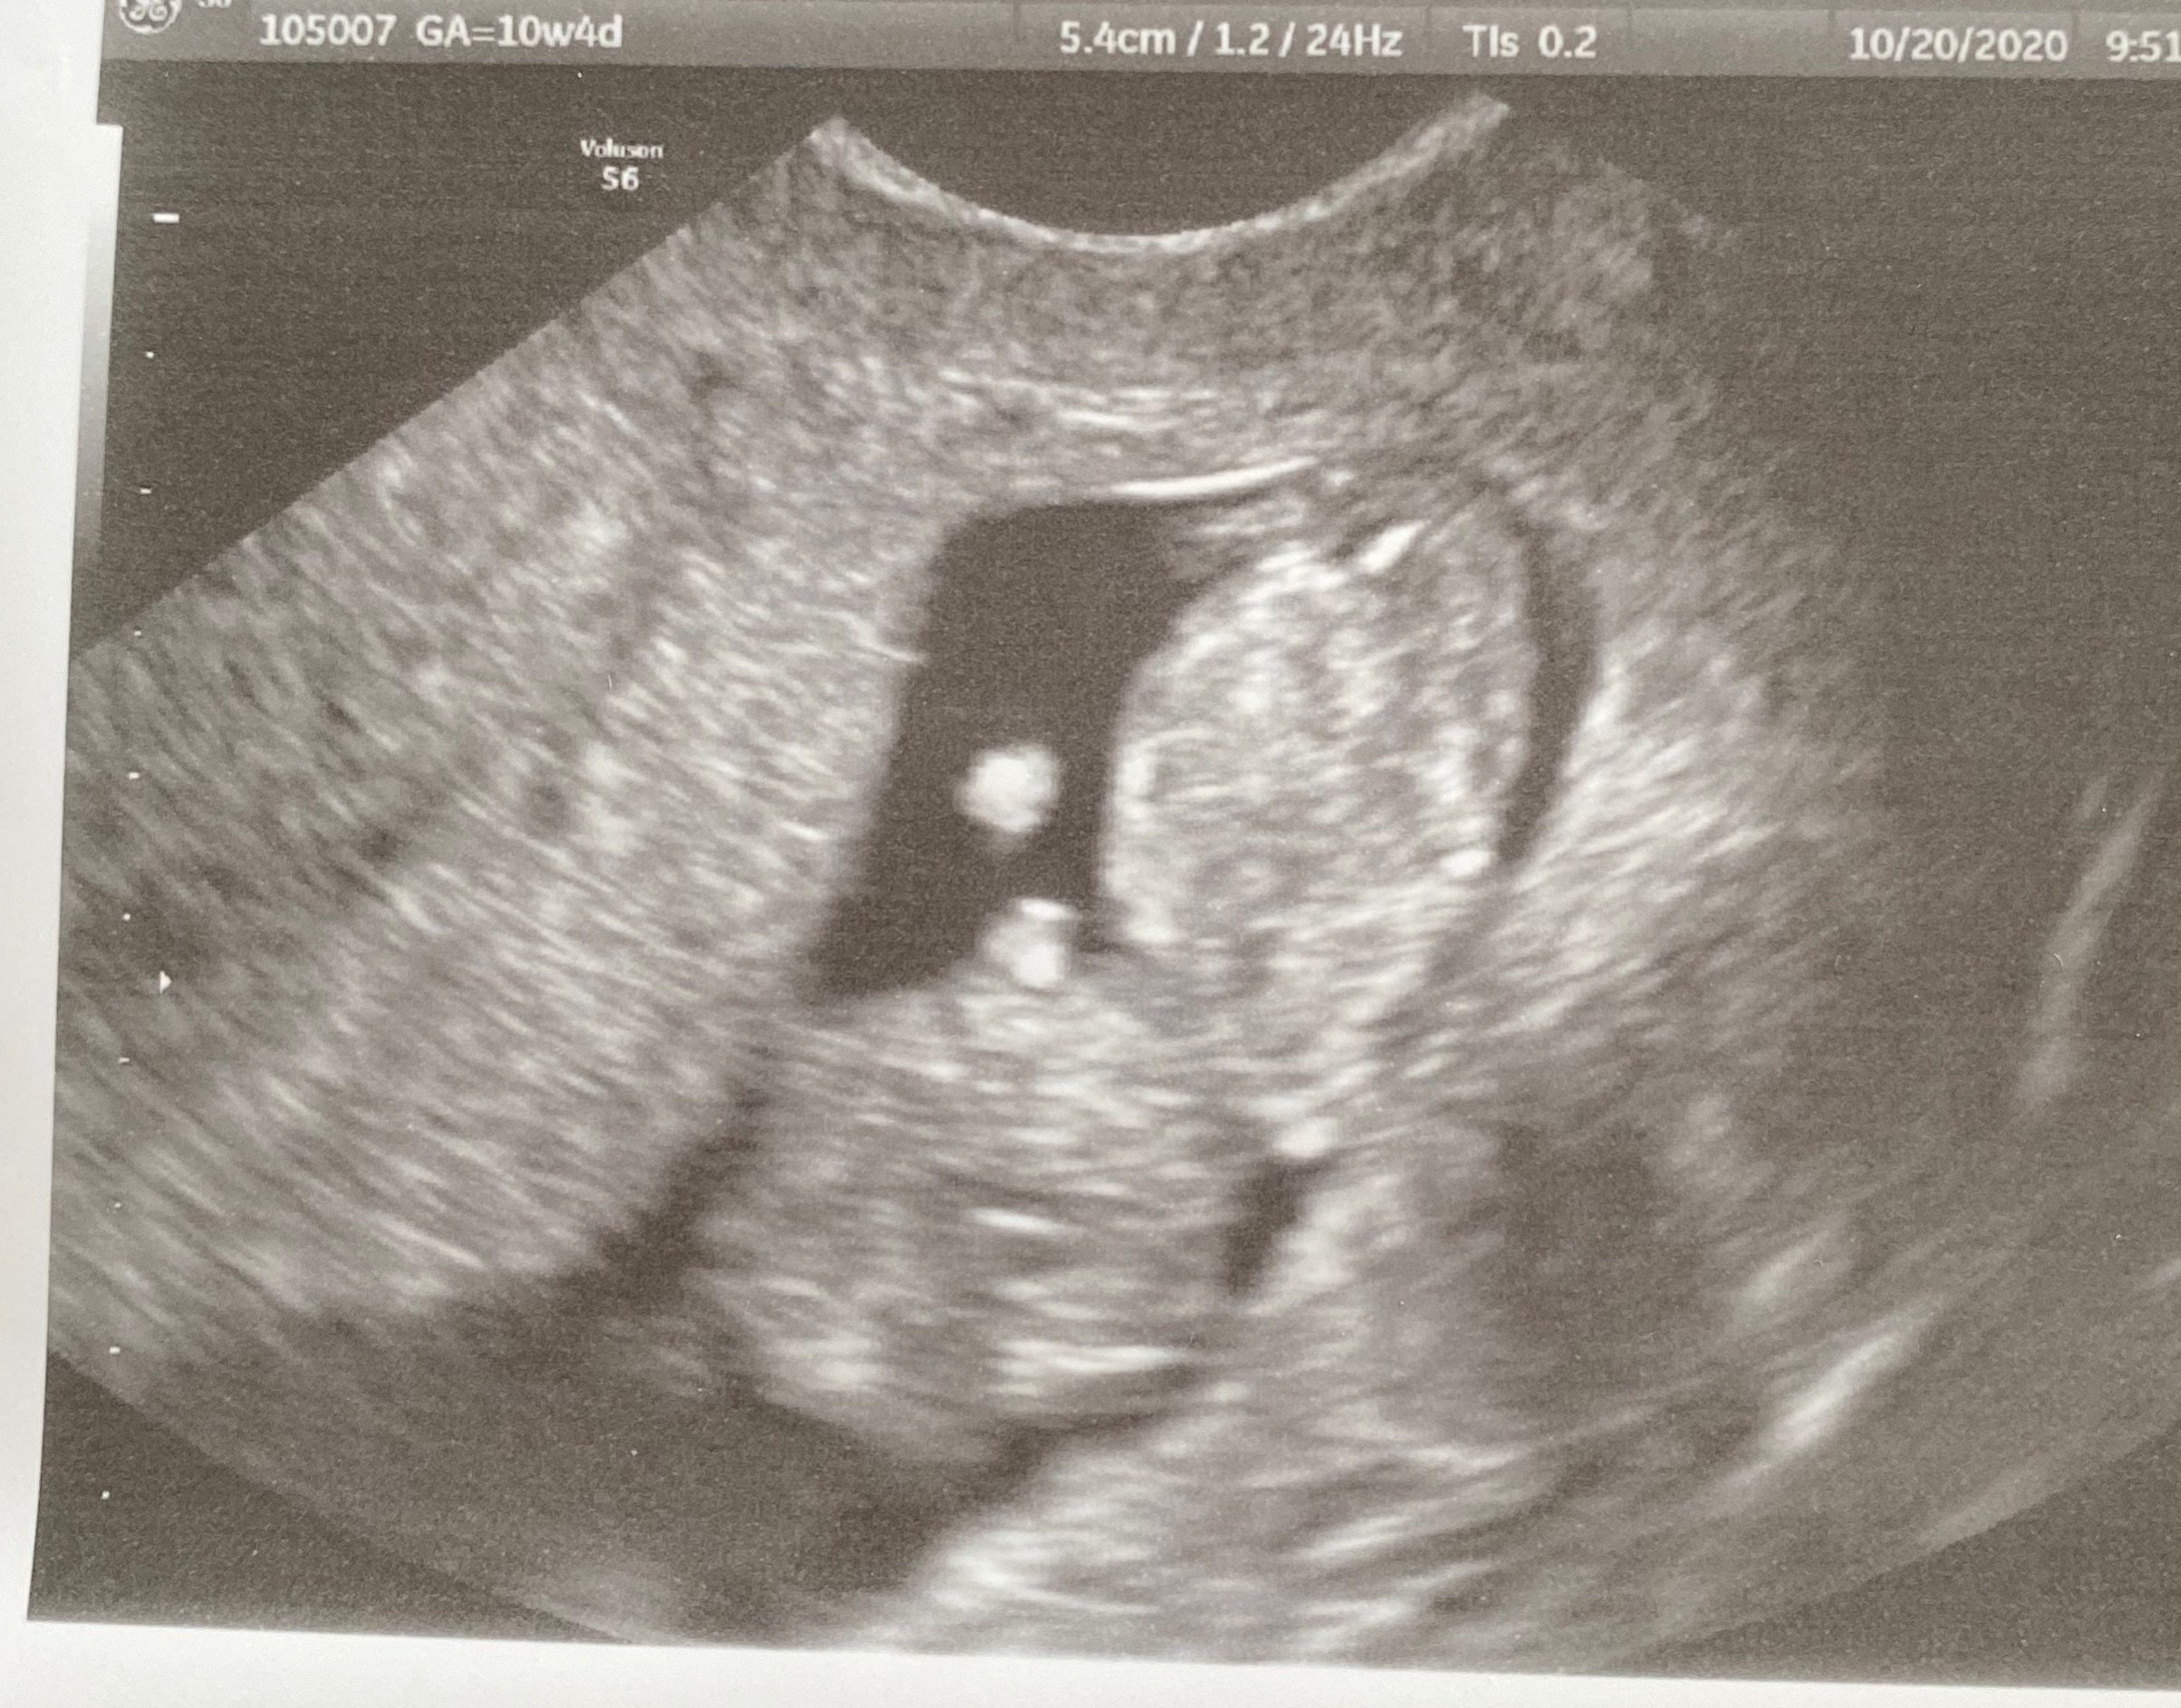

10+4!! Lil nugget was waving its arms around today, made it hard to get a good pic. 😍 babe looks good. One of my fibroids got a little bigger, and I have a cyst - OB wants the lab to look at both next week when I go in for NIPT bloods and scan.